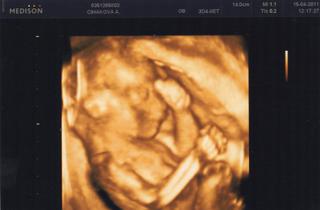

Ahoj holky, hlásím se z kontroly - všechno v pořádku! 😵 😵 😵 Máme hezké fotečky z 3D. Ale jinak stále nevíme, jestli kluk nebo holčička 😅 . Nejdřív doktor říkal, že to vypadá asi na kluka a potom,že spíš zas na holku, ale bylo to špatně vidět, takže prostě nevíme 🙂 . Hlavně že je všechno ok (ale teda já jsem tak zvědavá, ach jo 😀 )

@aja.83 páni krásné fotečky gratuluji 😵 😵 podle foteček mi to přijde na holčičku má jemnjěší rysy 😉 ale jasně že jen tipuji!!ty už jsi 21tt 😕 😵 😵 😵 to je pecka!!!!!!!!!!!!